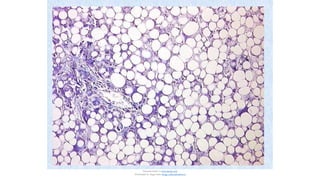

Esteatosis (cambio graso): Acumulaciones de

•

trigliceridos dentro de cell parenquimatosas

Se da en distintos organos:higado, corazon,

musculo y riñon

Causas: toxicas, malnutricion proteica,DM,

obesidad y anoxia

El alcohol es una hepatotoxina que altera las

funciones mitocondrial y microsomal

La malnutricion proteica actuan

disminuyendo la sintesis de apoproteinas

La anoxia inhibe la oxidacion de acidos grasos